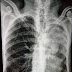

Casos Clínicos: Varón de 67 años con hemoptisis.

Buenas noches colegas les comparto la siguiente imagen. Paciente de 67 años cursando desde hace 1 mes con tos seca persistente, y los últi...